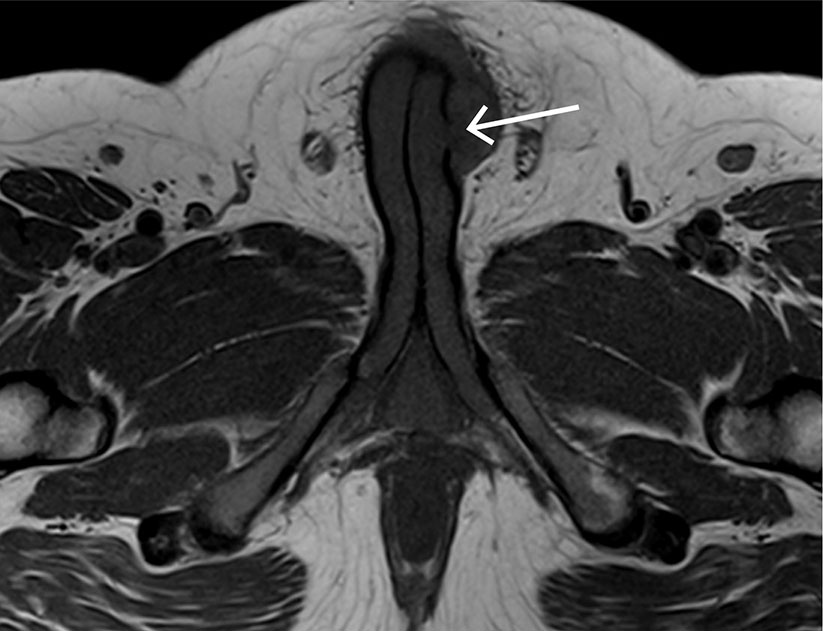

Det aksialt T1-vektede MR-bildet viser en penis der det på venstre side av penisroten foreligger en diskontinuitet i tunica albuginea forenlig med fraktur. Umiddelbart an mot frakturen ligger et hematom.

Mannen i 20-årene ble innlagt etter traume mot penis. Han beskrev å ha falt med vridningstraume mot erigert penis samme dag, hadde hørt et «knepp» og deretter fått lokale smerter og et blålig hematom. Smertene avtok med ereksjonen, men ved gjentatt ereksjon kom smertene tilbake. Pasienten oppgav normal vannlating, og urinstiks i akuttmottaket var negativ for hematuri. Ultralyd styrket mistanken om penisfraktur. Ved første operasjon ble det ikke avdekket noen sikker defekt, og videre MR-undersøkelse bekreftet ruptur. Ved ny operasjon tre dager etter innleggelse ble en centimeterstor defekt suturert.

Penisfraktur er en sjelden akutt urologisk tilstand, som krever akutt innleggelse og som oftest rask kirurgisk intervensjon (1). Frakturen er en ruptur i tunica albuginea av corpus cavernosum forårsaket av traume mot erigert penis, oftest sett i forbindelse med samleie (1). Diagnosen stilles ut fra anamnese og kliniske funn. Det mest typiske funnet kalles auberginetegn grunnet klinisk utseende med utbredt hevelse og hematom, men vår pasient hadde kun lokalisert hevelse og misfarging. Ultralyd kan være til hjelp, men MR-undersøkelse er foretrukket og gir tydelig fremstilling av rupturens størrelse og lokalisering (1). Det er viktig å avklare om rupturen går helt inn til urinrøret, som avgjør hvor rask kirurgisk intervensjon som er indisert.